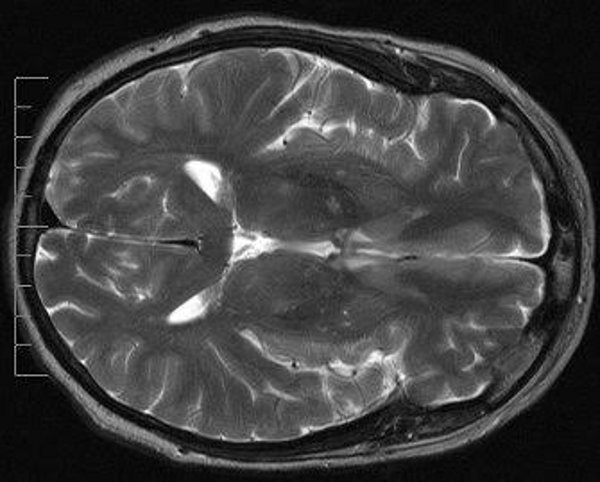

His algorithm yields an immediate decision, 'malignant' or 'benign', shortcutting the usual month-long waiting time for lab analysis of a biopsy tissue-sample: instead it mathematically analyzes 13 characteristics of the texture context in an MRI image.

Dragos tested his result using a large public database of patient MRI images and determined that his algorithm had a 90-percent accuracy-rate.